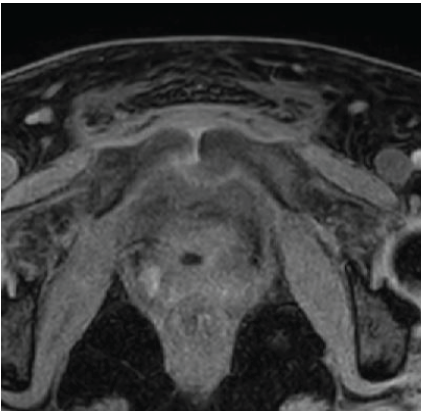

When MRSA Misleads: Tuberculous Osteomyelitis of the Anterior Pelvic Bones

Sanjana Nair , Vinod Xavier , Nishma Monteiro , Renji Jos , S Roshan

………………………………p.153-157